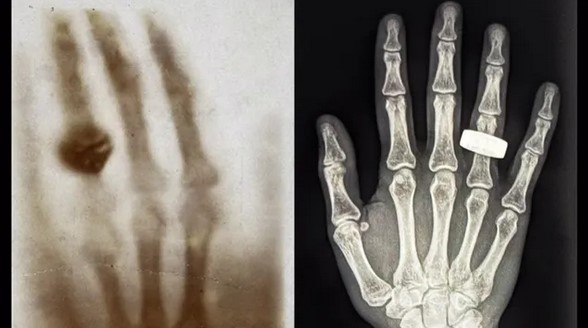

1895 року фізик Вільгельм Рентген уперше відкрив рентгенівські промені та зрозумів, що вони можуть бути корисними для медицини. У підсумку вчений зробив перший в історії рентгенівський знімок людського тіла. Це було зображення руки його дружини з обручкою. Через 130 років учасники місії Fram2 відтворили цю рентгенівську фотографію, але вже в космосі.

Перший рентгенівський знімок людини в космосі було зроблено під час місії Fram2 (праворуч). Екіпаж місії Fram2 вирішив віддати данину поваги найпершому рентгенівському знімку, на якому було зображено руку з кільцем (ліворуч)

Фото: Starship